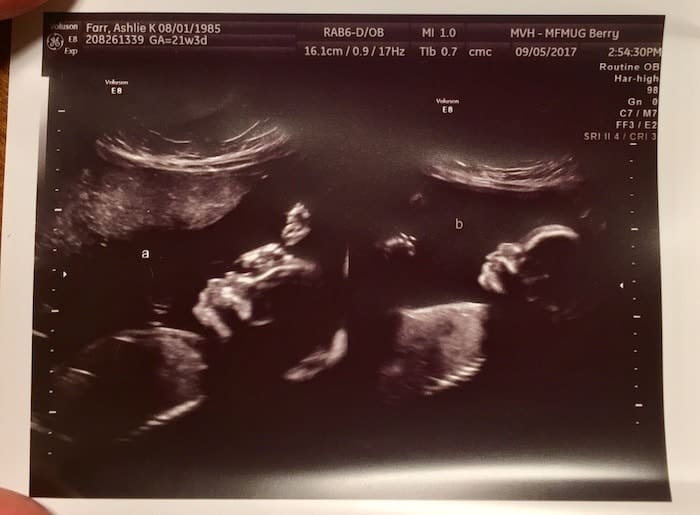

Between weeks 18-22 you’ll have a level 2 anatomy scan. This is when you can typically find out the sex(es) of your babies. Don’t be surprised, however, if it’s too difficult to see one or both babies’ genitalia to determine the sex, most often because of the position the babies are in. During this scan, your medical team will be assessing the development of each baby’s brain, face, heart, spine, and other major organs, as well as the placement of the placenta(s), umbilical cords, and amniotic fluid levels. Do not be surprised if you are asked to come back for a follow-up scan. This is very common with multiple birth pregnancies because it’s often difficult for the technician to get a good picture if your babies are not cooperating.

Ultrasound Photos at 21 Weeks Pregnant With Twins